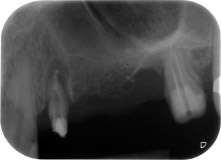

Fig. 1: Paziente di 58 anni. La radiografia preoperatoria mostra una lesione periodontale apicale in corrispondenza del dente 24 e una perdita orizzontale di tessuto osseo alveolare nel secondo quadrante.

Una paziente donna di 58 anni lamentava dolore e aumentata mobilità del dente di appoggio del ponte 24. Era presente infiammazione periodontale con tasche di profondità di 7 mm a livello mesiobuccale e di più di 12 mm a livello distale, nonché coinvolgimento di terzo grado della forcazione. Inoltre, la radiografia rivelava una lesione periodontale estensiva attorno alla regione apicale del dente pretrattato 24 (in altro luogo) a livello endodontico (Fig. 1).

Un anno più tardi, sono stati estratti i denti 25 e 26 in seguito a trauma e per motivi endoperiodontali, prima del posizionamento del ponte. Era stata diagnosticata una lesione endoperiodontale combinata in corrispondenza del dente 24, di eziologia incerta. La paziente desiderava conservare i denti 24 e 27 di appoggio al ponte e non accettava una protesi rimovibile finale, o temporanea. Si è pertanto deciso di fare il possibile per conservare entrambi i denti, nonostante la prognosi negativa basata sugli esiti clinici e radiologici.